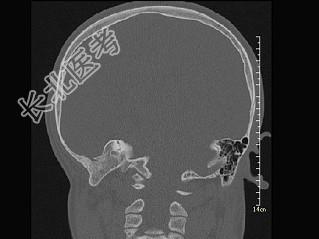

- 单项选择题女,12岁, 自幼右侧听力丧失,CT检查如图, 下列说法错误的是 ( )

A、右侧外耳道闭锁

B、右侧外耳道不发育

C、右侧慢性化脓性中耳炎

D、右侧乳突为板障型

E、应诊断为先天性外耳道畸形